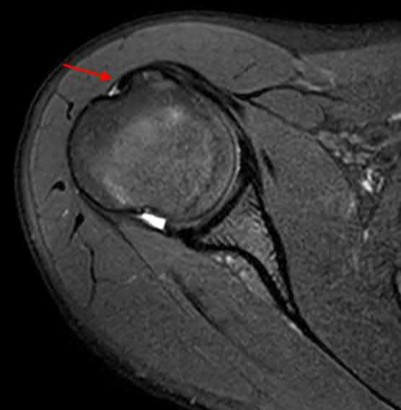

Question 12

A 55-year-old patient presents with a slowly enlarging, painful mass in the proximal humerus.

Biopsy reveals a hyaline cartilage matrix with cellular atypia, confirming a diagnosis of central conventional chondrosarcoma. Which of the following genetic mutations is most frequently identified in this specific tumor?

Explanation

Mutations in the isocitrate dehydrogenase genes, IDH1 and IDH2, are found in up to 50-60% of central conventional chondrosarcomas and enchondromas. EXT1 and EXT2 mutations are characteristic of multiple hereditary exostoses (osteochondromas). GNAS mutations are seen in fibrous dysplasia. TP53 and RB1 mutations are hallmark aberrations in osteosarcoma.